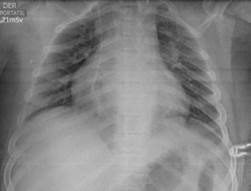

At 48 hours, MSSA was isolated in bone and blood cultures, and antibiotic therapy was redirected to oxacillin 160 mg/kg/day; however, four days after admission, the patient presented with reappearance of fever, increase in lower limb edema and elevation of acute phase reactants with persistent isolation in blood cultures, so the search for the foci of the disseminated infection was initiated. Since deep vein thrombosis in one of the posterior tibial veins was observed in the Doppler ultrasound of the lower limb (Figure 1), anticoagulation with dalteparin was initiated and management with oxacillin continued for 42 days with satisfactory evolution and recovered renal function upon discharge.

Doppler ultrasound: left posterior tibial vein (PTV) thrombosis.

Figure 1: Doppler ultrasound: left posterior tibial vein (PTV) thrombosis.

Source: Document obtained during the study.